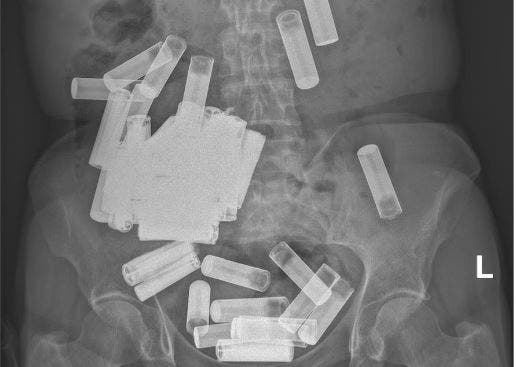

Desafortunadamente, una radiografía reveló que eran 55 las baterías en su abdomen, aunque afortunadamente ninguna parecía estar obstruyendo su tracto gastrointestinal.

Durante un período de una semana, defecó cinco pilas AA, sin embargo, las radiografías seguían mostrando que la gran mayoría de las pilas no habían podido seguir avanzando por hacia el recto. En ese momento, la mujer comenzó con dolor abdominal.

Este extraño caso fue documentado por la revista Irish Medical Journal, donde se da cuenta de que la mujer se tragó 55 pilas AA y AAA y debieron hacer una laparotomía para extraerlas.